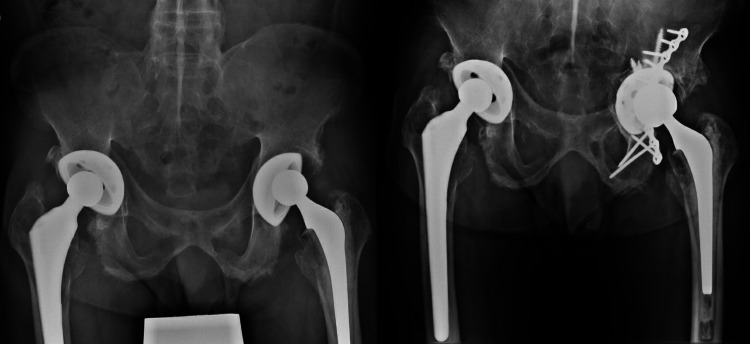

Methods: A total of 71 hips in 58 patients receiving the same model of cementless component without screw holes (Depuy Duraloc 100 hydroxyapatite (HA) component) from June 1999 to March 2003 were prospectively followed up. All patients were allowed to have immediate full weightbearing. The mean age at THA was 53.7 years (28 to 74). Osteonecrosis was the leading cause of THA. Survival was assessed with any revision and component revision as the endpoint. Radiological parameters, including lateral opening angle, and the components' vertical and horizontal migration distances, were measured and compared between the early postoperative period and final follow-up.

Results: Overall, 54 hips were assessed at a minimum 20-year follow-up. The mean follow-up was 22.9 years (20.9 to 24.5). Two component revisions occurred at 17.5 and 17.6 years later. Both components were well fixed but were revised, due to the need to upsize the articulation and component malpositioning, respectively. Conventional polyethylene (PE) was used in both hips, and 14 other hips were revised with the components well fixed and not revised. The estimated survival of the acetabular component and THA at 20 years was 96.4% and 74.5%, respectively. Mean changes in lateral opening angle and vertical and horizontal migration distances were 0.48° (SD 1.45°), -0.06 mm (SD 1.44), and -0.36 mm (SD 1.36), respectively, with no statistical significance.

Conclusion: This study provides evidence of excellent long-term survival of cementless components without screw holes. Immediate postoperative weightbearing did not lead to component migration in the long term.